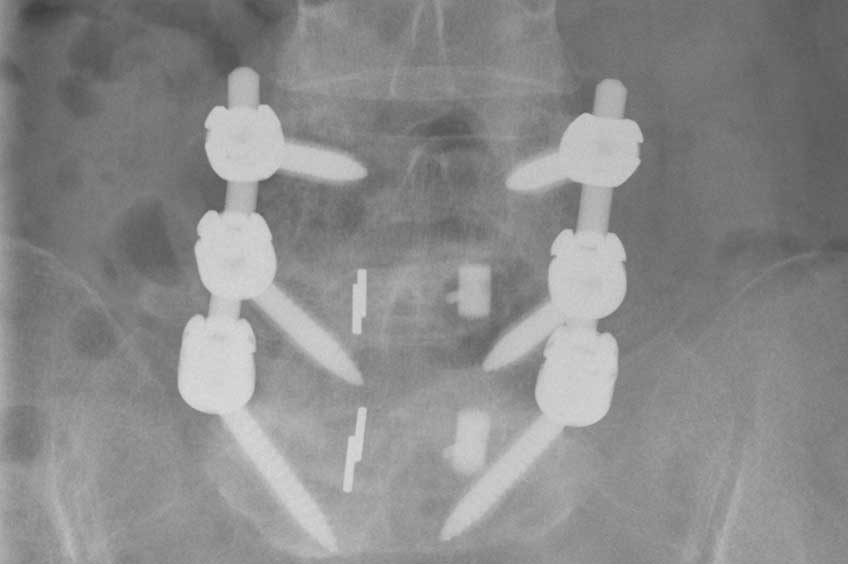

- Titanschrauben werden präzise in die Wirbelkörper eingebracht und mit Längsstangen verbunden

- Zur Versteifung wird Knochenmaterial auf den Querfortsätzen der Wirbelkörper und zwischen den Facettengelenken (Gelenke, die die Wirbelkörper verbinden) angelagert

Stabilisation der Wirbelsäule mit Titanschrauben und Knochenanlagerungen. Erweiterter Spinalkanal, um komprimierte Nerven freizulegen.

Zur zusätzlichen Stabilisation werden in vielen Fällen sogenannte Cages (Titankörbchen) mit Knochenmaterial in den Bandscheibenraum eingesetzt. Dieser Eingriff kann ebenfalls rückseitig oder über einen zusätzlichen seitlichen bzw. vorderen Zugang erfolgen.

Zusätzliche Stabilisation der Wirbelsäule durch Implantation von Cages zwischen den Wirbelkörpern